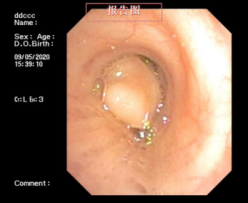

近日,一位患支气管肿瘤患者到我院呼吸内科治疗,检查时,其肿瘤几乎已经完全堵塞气管管腔,若不及时手术,随时可能发生呼吸衰竭。

情况危急,医生立即为其抽取动脉血化验并给予高流量吸氧等,但患者呼吸困难的症状缓解不明显,必须及时将肿瘤切除。“如果按照传统的手术方式,需将患者气管切开,组织损伤性高、流血量多。由于患者肿瘤贴近降主动脉,切除过程中将伴有大出血的风险。”刘碧翠说,随着我院内镜技术的发展,对于这样的重症患者,可以利用呼吸内镜迅速切除肿瘤,清理气道内局部的坏死组织、分泌物并予以止血处理。

科室介入团队经过精心准备后,立刻为患者实施内镜介入手术,将气道内肿物切除干净。手术仅用时2小时,患者没有发生大出血,很快便恢复出院。此次手术的成功开展,充分体现了呼吸内科对此类疑难危重气道疾病患者的救治能力。